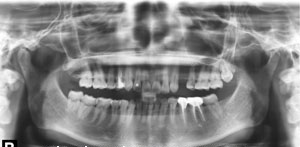

Chụp phim Panorama kiểm tra

![]() |

| Phim Panorama |

Dựa trên phim Panorama ta có thể thấy R24 bị tiêu xương ổ răng do mất răng lâu ngày

Kế hoạch điều trị: cấy 1 implant nâng đỡ R24, ghép xương

Kiểm tra mật độ xuơng ổ R24 trên phim CT 3 chiều và phần mềm cấy ghép Implant